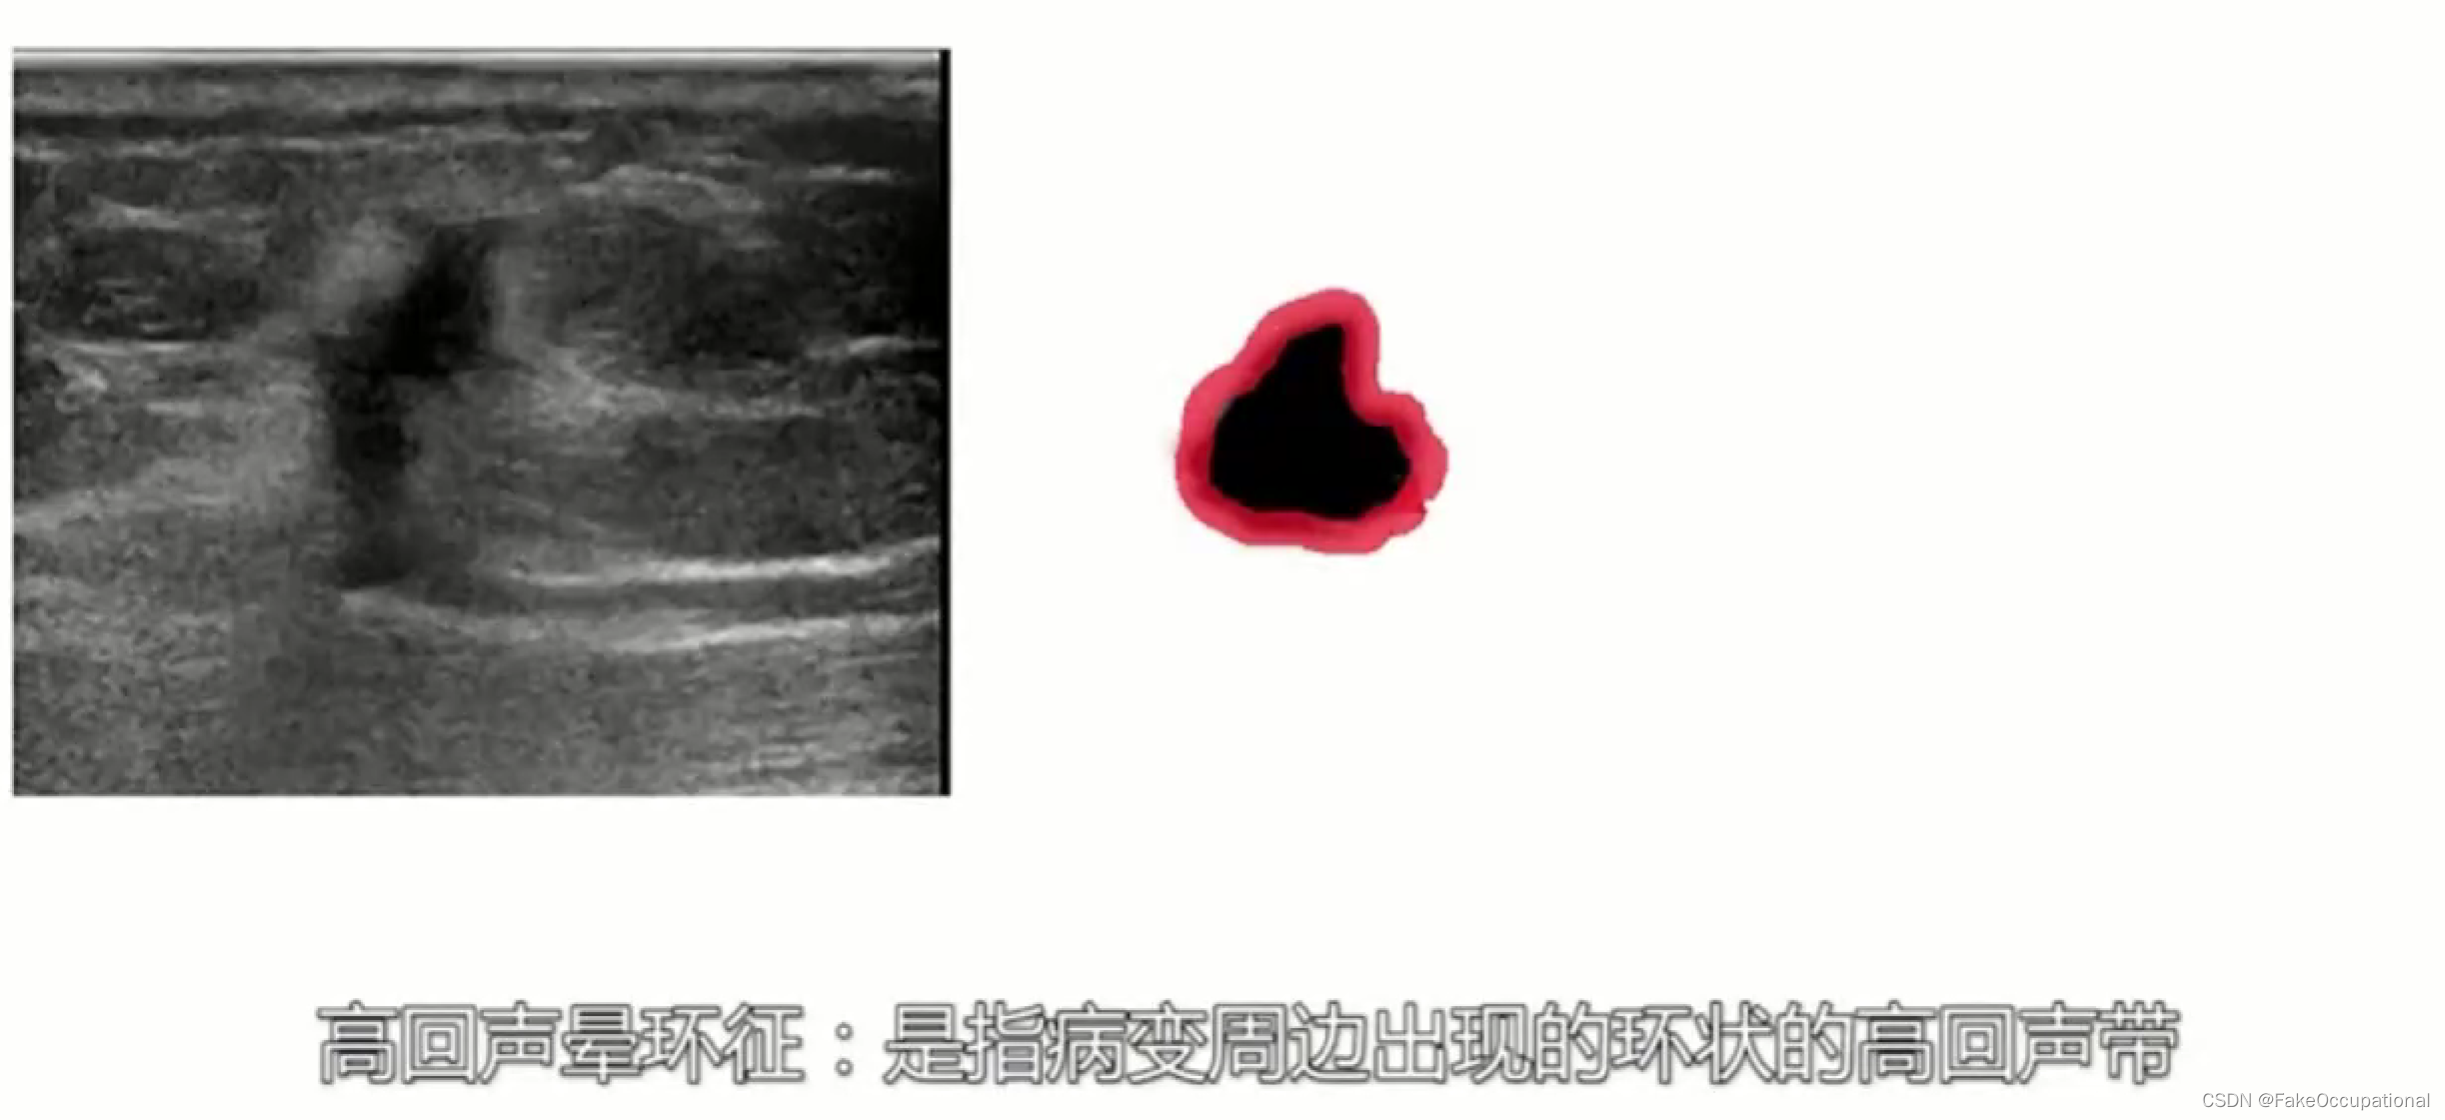

乳腺癌

- 患者18岁,微小癌

- 其理论依据是恶性肿瘤常星离心性生长

- 淋巴结转移